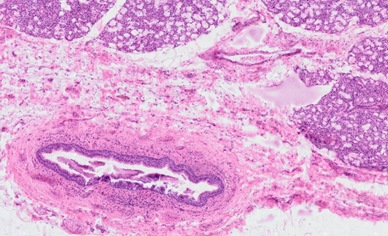

A 9-year-old girl comes to the dentist with her

mother. A large swelling, even a cyst, is forming under her tongue. It is a

so-called ranula, which is a retention cyst of the sublingual gland, formed by

obliteration (closure) of the duct, probably as a result of a previous

infection. The outflow of the saliva produced is impossible. The stagnant

saliva dilates the ducts, forming a secretion-filled cyst. The treatment here

is extirpation (surgical removal). Which characteristic describes the closed

main duct of the salivary gland here?